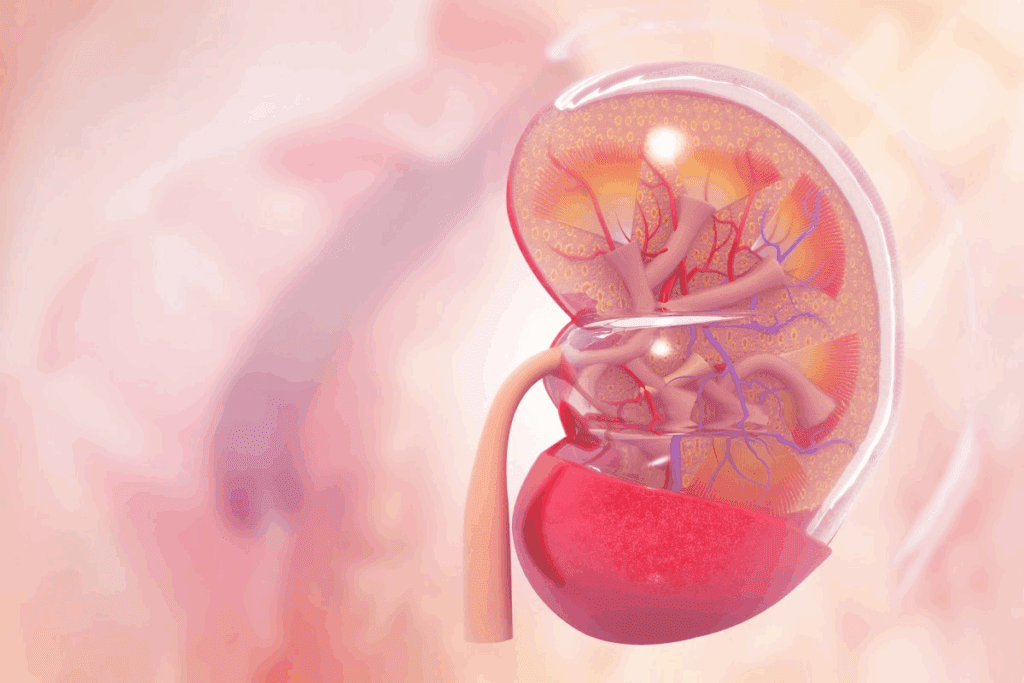

It’s important to know about calcium phosphate kidney stones. They are made of calcium phosphate in different forms. This affects how they behave and how to treat them.

Calcium phosphate stones come in two main types: hydroxyapatite and brushite. Hydroxyapatite is less soluble and often found in alkaline urine. Brushite, on the other hand, is more soluble and forms in less alkaline urine.

Knowing the difference between these forms is key. It helps understand how the stone grows and how to treat it. For example, hydroxyapatite stones are linked to high urine pH levels.

Calcium phosphate stones are different from calcium oxalate stones. Both are calcium-based, but their structures and growth patterns are not the same. Calcium phosphate stones are irregular and can damage kidney tissue.

Calcium oxalate stones, on the other hand, have a more uniform structure. The differences in structure and composition are important for treatment and prevention.

Calcium phosphate stones grow in different ways. Their growth is influenced by urine pH, calcium levels, and other minerals. They can grow fast, which is a problem in alkaline urine.

The size of these stones can vary. They can be small and not cause symptoms or large and block the kidney. Knowing how they grow helps predict problems and plan treatments.

To understand how calcium phosphate stones form, we need to look at several key factors. The process starts with the crystallization of calcium phosphate in urine. This can happen in different forms, like hydroxyapatite and brushite.

Crystallization of calcium phosphate depends a lot on urine pH. In alkaline urine, calcium phosphate is less soluble. This makes it more likely for crystals to form. High urine pH is a big risk for these stones.